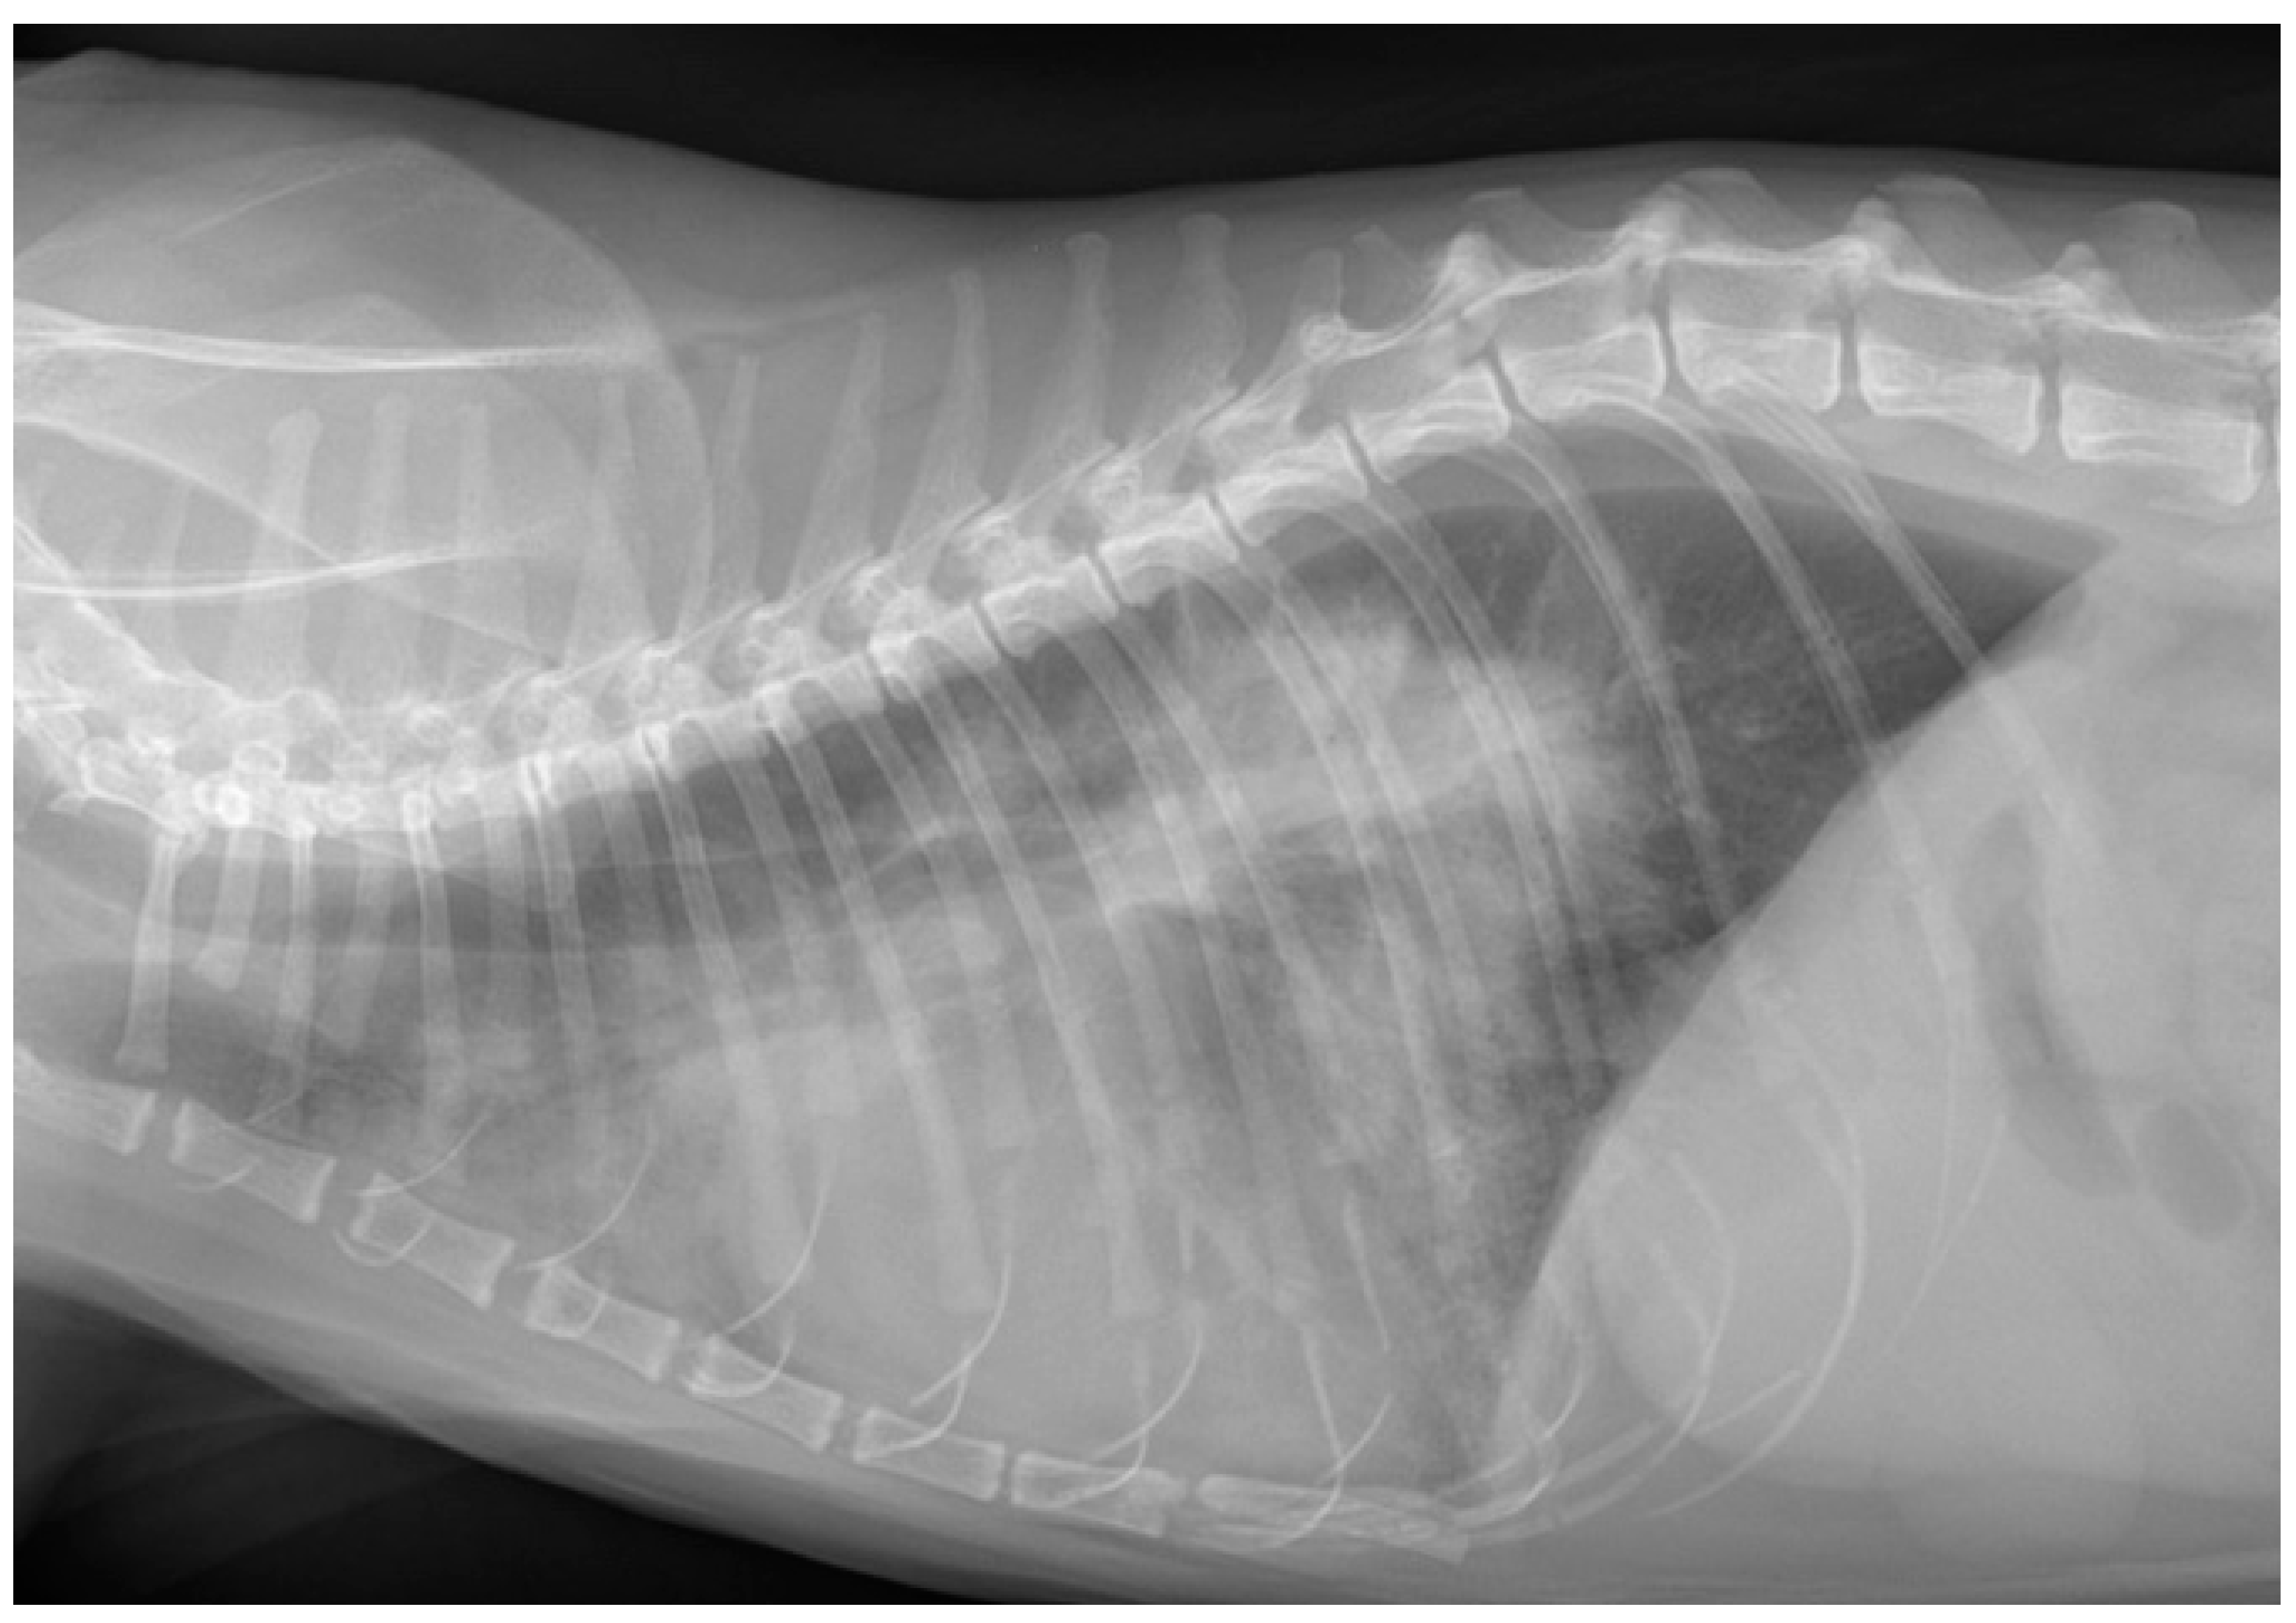

- Pleural effusions